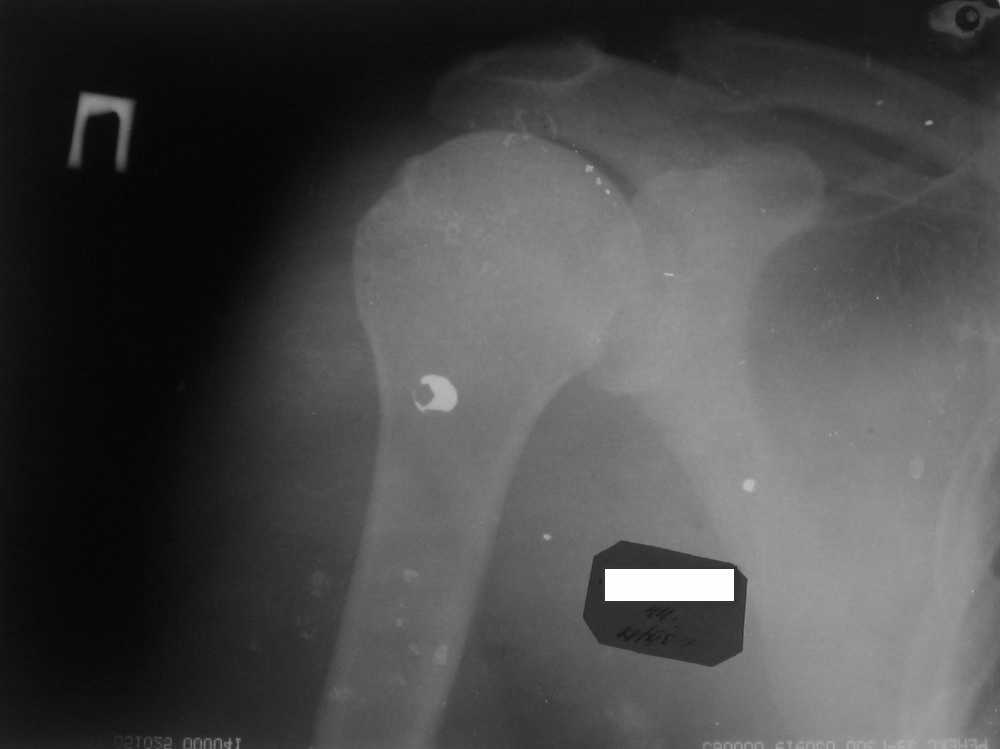

Судя по снимкам, у вашего пациента артрит АС сустава.

сделайте тест с лидокаином внутри суставно - если боли купируются при выполнении нагрузок, то АС резекция 0,6-0,8 см решит проблему. Если боли не

уходят, и вы при осмотре сустава находите симптомы субакромиального импинджмента, попросите рентгенологов косую проекцию(Neer's view).

Наличие экзостоза по передне-нижней поверхности акромиона в сочетании с клиническими симптомами определит тактику. случается, что экзостозь не

сформирован, но симптомы субакромиального импинджмента оперделяются при осмотре (болезненна фаза разгибания и внутренней ротации плеча). В такой ситуации причиной болей является дегенеративное воспаление корако-акромиальной связки. Если локальная инъекция стероидов с анестетиком, нестероидные противовоспалительные препараты, физио не устраняет болей, то резекция связки восстанавливает безболезненность движения.

Но могу добавить, что у данной группы спортсменов часты разрывы вращающей манжеты плеча, причем достаточно сложные для реинсерции - с расслоением сухожилий. Видимо это связано с приемом анаболических стероидов. Я имел честь оперировать двоих "культуристов" такого возраста.

Советую сделать контрастную артрографию или, если это доступно, контрастную артрографию в условиях спирального компьютерного томографа. Надеюсь, Вы получите ответ и вопрос "Что делать?" разрешится сам собой.